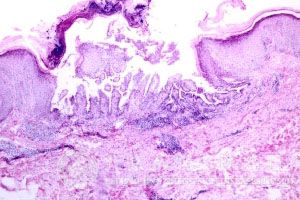

北京京城皮肤医院指出,黄水疮的诊断一般都是根据损害的临床特点、发病季节、年龄、部位、基本损害为脓疱,黄水疮患者发病部位脓疱周围有红晕,疱液上清下浊,愈后,由于黄水疮的传染性强,所以大家要重视起来疾病的预防、治疗、护理等方面的工作,是为了自己的健康着想,也是为了其他人的健康考虑。

在进行黄水疮疾病的实验室检查中,可以看出白*总数及中性粒*可增高,脓液细菌培养为金黄色葡萄球菌和链球菌等特点,提醒只要细心的观察其发病特点,还是不难诊断黄水疮疾病的。